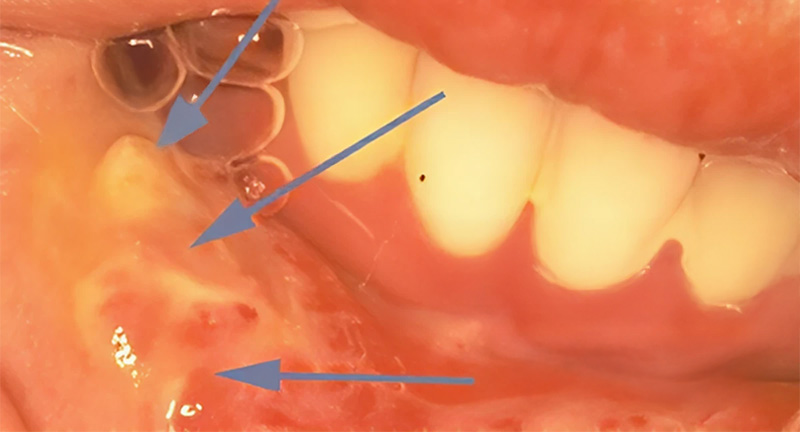

Fig. 04.

Fig. 04.

L’endocuriethérapie est une irradiation in situ : des aiguilles de césium 132 ou d’irridium (IR 192) radioactifs sont mis en place dans la tumeur. Ces aiguilles sont laissées en place 8 à 10 jours, délivrant environ 70 Grays. Les mucites peuvent être très invalidantes.